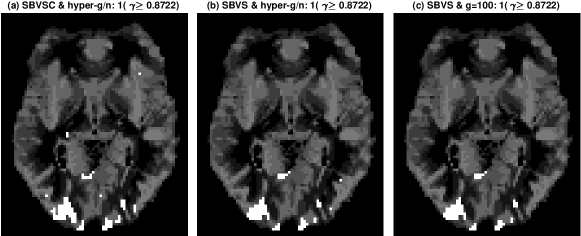

Figure 4: Posterior activation and amplitude maps for the fMRI data from three different estimators. The first row shows the activation maps (where white voxels are those classified as active), and the second shows the mean activation amplitudes. The three different estimators are: (a,d) SBVSC with hyper-g/n prior; (b,e) SBVS with hyper-g/n prior; and, (c,f) SBVS with g=100𝑔100g=100. This figure appears in color in the electronic version of this article, and any mention of color refers to that version.

Based on these observations, Figure 4 compares activation and amplitude maps for three cases: panels (a,d) SBVSC with hyper-g/n prior; (b,e) SBVS with hyper-g/n prior; and (c,f) SBVS with g=100𝑔100g=100. The latter case is included because it is the benchmark model suggested by Smith and Fahrmeir (2007). The activation maps in the first row are obtained by defining a voxel as active if and only if Pr(γi=1|𝒙,𝑾,𝒚)0.8722Prsubscript𝛾𝑖conditional1𝒙𝑾𝒚0.8722\mbox{Pr}(\gamma_{i}=1|\text{\boldmath$x$},\bm{W},\text{\boldmath$y$})\geq 0.8722. The justification for this threshold value is that 2log((1Pr(γi=1|𝒙,𝑾,𝒚))/Pr(γi=1|𝒙,𝑾,𝒚)-2\log((1-\mbox{Pr}(\gamma_{i}=1|\text{\boldmath$x$},\bm{W},\text{\boldmath$y$}))/\mbox{Pr}(\gamma_{i}=1|\text{\boldmath$x$},\bm{W},\text{\boldmath$y$}) is approximately χ2(1)superscript𝜒21\chi^{2}(1) distributed and the threshold corresponds to a p-value of 0.05. The maps for the two SBVS models are close to identical, but differ from those for the SBVSC model, with the latter allowing for sharper edges in the amplitude maps. To further highlight this difference, Figure 5 plots the difference in the activation probabilities between the copula and Gaussian models. These differ between -0.6 and 0.6, so that allowing for more accurate marginal calibration of the MR signal not only increases the logarithmic scores, but affects activation maps, which are the primary output of fMRI processing.